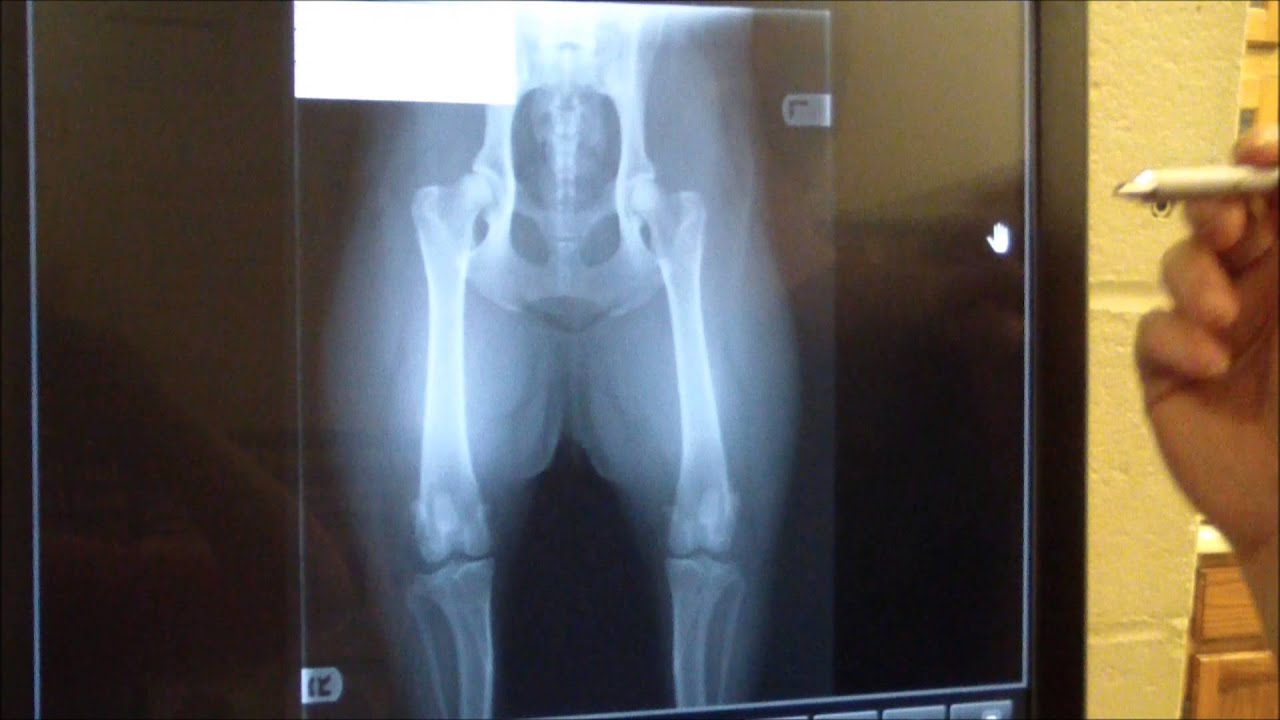

Ofa Visual Grounding A Hugging Face Space By Ofa Sys Each study will be discussed in detail including anatomic landmarks for collimation, visuals to demonstrate what is straight crooked and tips on how to achieve a properly positioned orthopedic radiograph using hands free techniques the first time. Learn about x ray positioning for accurate ofa hip dysplasia grading in dogs. improve diagnosis with proper techniques. This article discusses the detrimental impact that an incorrectly positioned x ray can have on the accurate diagnosis of hip dysplasia or hip grading and certification. The case is explored empirically in a study of 200 dogs initially submitted to ofa for hip grading and then resubmitted to ofa after follow ‐up x ‐rays were taken using the precise positioning technique® developed by the first author.

X Ray Positioning In Ofa Hip Dysplasia Grading This article discusses the detrimental impact that an incorrectly positioned x ray can have on the accurate diagnosis of hip dysplasia or hip grading and certification. The case is explored empirically in a study of 200 dogs initially submitted to ofa for hip grading and then resubmitted to ofa after follow ‐up x ‐rays were taken using the precise positioning technique® developed by the first author. You are required to first have the veterinarian provide me with a copy of your dog's xray, to determine if the position is acceptable and whether xrays should be sent in for evaluation. With chemical restraint, optimum patient positioning is easier with minimal repeat radiographs (less radiation exposure) and a truer representation of the hip status is obtained. Radiographs submitted to the ofa should follow the american veterinary medical association recommendations for positioning. this view is accepted worldwide for the detection and assessment of hip joint irregularities and secondary arthritic hip joint changes. Now to analyze an x ray that was rated ofa excellent. note: remember the dog is laying on it’s back when the x rays are taken, so left is right and right is left.